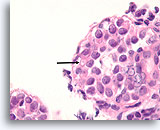

Papilloom, Borst FNA, Celblok.

Door histologische coupes te maken, kunnen de samenstelling, architectuur en cytologische kenmerken van de grotere papillaire fragmenten bestudeerd worden. Myoepitheliale cellen zijn duidelijk aanwezig (pijlen) en en wordt geen stratificatie van de ductale cellen waargenomen.

60X

Papilloom, Borst FNA, Celblok.

Door histologische coupes te maken, kunnen de samenstelling, architectuur en cytologische kenmerken van de grotere papillaire fragmenten bestudeerd worden. Myoepitheliale cellen zijn duidelijk aanwezig (pijlen) en en wordt geen stratificatie van de ductale cellen waargenomen.

60X